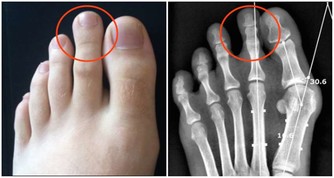

3難以形容的持續痛

如果身體某一部位突然疼痛,持續一個多星期,應盡快查明原因。例如,長期腹痛是大腸癌的症狀;胸痛可能是肺癌引起的;骨痛可能是癌症轉移的症狀。這時,我們應該去醫院找醫生檢查一下。